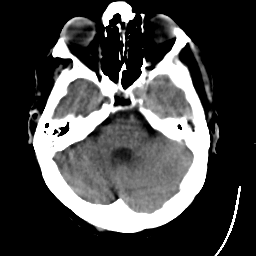

Meningioma: Roentgen-ray CT #1 -- Slice #5

[Home][Help][Clinical] Slice 5